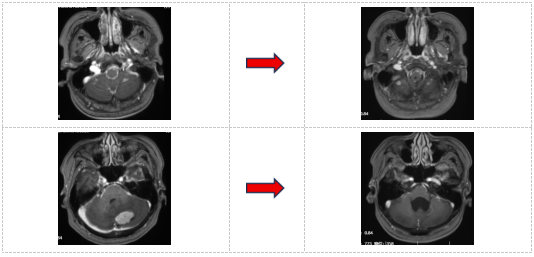

2025年3月31日,患者第四次入院,复查颅脑MR提示:脑内、软脑膜、延髓可见多发异常强化,提示多发转移瘤。根据病情变化,团队优化治疗方案,调整为塞替派联合德曲妥珠单抗治疗,以进一步强化靶向治疗效果。2025年6月10日,颅脑MR检查提示病情达到部分缓解(PR),脑膜转移灶较前明显改善,患者临床症状显著缓解。德曲妥珠单抗是一种HER2靶向抗体与DNA拓扑异构酶I抑制剂偶联物,用于治疗HER2表达的实体瘤,包括乳腺癌、胃癌、结直肠癌和非小细胞肺癌。

左:2025-3-31颅脑MR:脑内、软脑膜、延髓多发转移瘤。右:2025-6-10颅脑MR:病情达到部分缓解(PR)